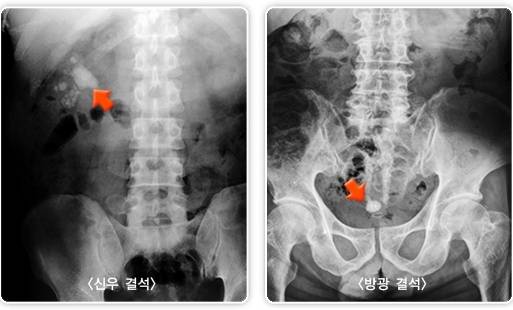

요로결석은 소변이 나오는 길(요로) 중 어느 부위에 발생했는지에 따라 △신장결석 △요관결석 △방광결석 △요도결석으로 구분된다. 통증이 극심하기로 유명한데, 보통 옆구리·복부에 칼·송곳으로 찌르는 듯한 격렬한 통증을 유발하며 진통제로도 쉽게 진정되지 않는다. 심하면 아랫배로 통증이 퍼지며, 혈뇨·탁뇨·빈뇨가 동반될 수 있다.